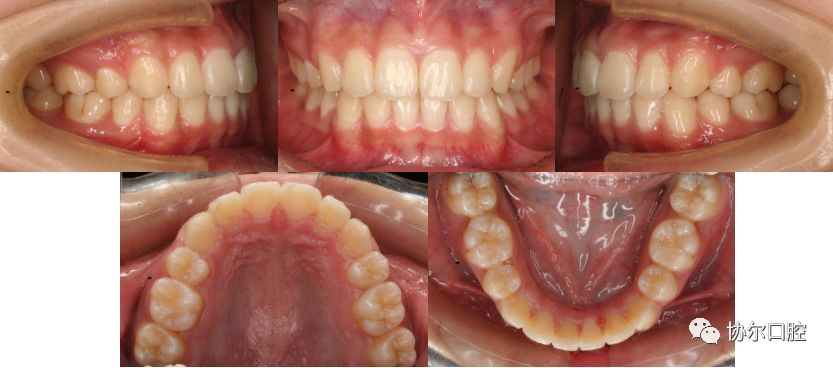

矫治前后对比

治疗前后对比